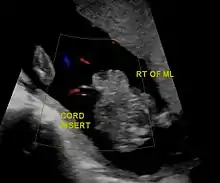

Diagnostic method | Ultrasound during pregnancy, based on symptom at birth[1] |

In the developed world, around 90% of cases are identified during normal ultrasound screens, usually in the second trimester.[17]